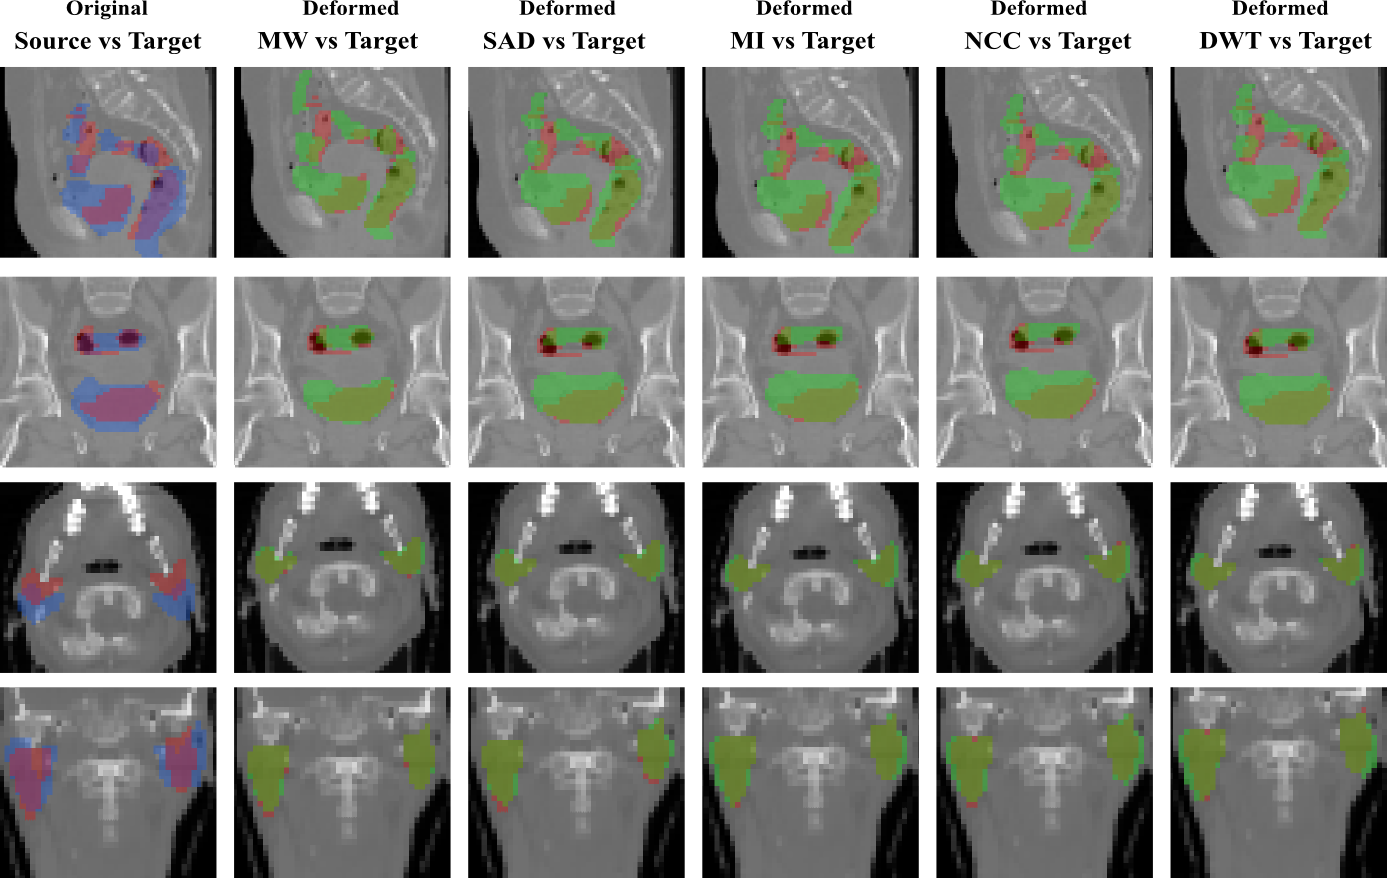

Refer to caption

Figure 3: Overlapping of the segmentation masks in different views for one registration case from RT Abdominal (first and second rows) and RT Parotids (third and fourth rows) datasets. The first column corresponds to the overlapping before registration between the source (in blue) and target (in red) segmentation masks of the different anatomical structures of both datasets. From second to sixth column, we observe the overlapping between the warped source (in green) and the target (in red) segmentation masks, for the multi-weight algorithm (MW) and for the single metric algorithm using sum of absolute differences (SAD), mutual information (MI), normalized cross correlation (NCC) and discrete wavelet transform (DWT) as similarity measure.

RT Parotids It contains 888 CT volumes of head, obtained from 4 different patients, 2 volumes per patient. The volumes are captured in two different stages of a radiotherapy treatment in order to estimate the radiation dose. Right and left parotid glands were segmented by the specialists in every volume. The dimensions of the volumes are 56×62×5356625356\times 62\times 53 voxels with a physical spacing of 3.453.453.45mm, 3.453.453.45mm, and 444mm, in x, y, and z axes, respectively. We generated 888 pairs of source and target volumes using the given dataset. Notice that, while generating the source and target pairs, we did not mix the volumes coming from different patients. We split the dataset into train and test, and cross validated the hyper-parameters C𝐶C and α𝛼\alpha on the train dataset. The average result on the test dataset are shown in the Figure 5.a, while qualitative results can be found in Figure 3.

Figure 2 shows the examples of the slices from the 3D3𝐷3D volumes corresponding to each dataset. In figures 3 and 4 we include some qualitative results on the three challenging datasets in order to highlight the effects of learning the weights of different metrics. In the first one (figure 3), we present the overlapping of the segmentation masks in different views for one registration case from RT Abdominal and RT Parotids datasets, using single and multi-metric approaches. The observed results are coherent with the numerical results reported in figures 5.a and b. We observe that multi-weight algorithm gives a better fit between the deformed and ground truth structures than the rest of the single similarity measures, which are over segmenting most of the structures showing a poorer registration performance. In the second graph (figure 4), we include results for the IBSR dataset. Extreme values (which mean high differences between the images) correspond to blue and red colors, while green indicates no difference in terms of intensity. Note how most of the big differences observed in the first column (before registration) are reduced by the multi-weight algorithm, while some of them (specially in the peripheral area of the head) remain when using single metrics.